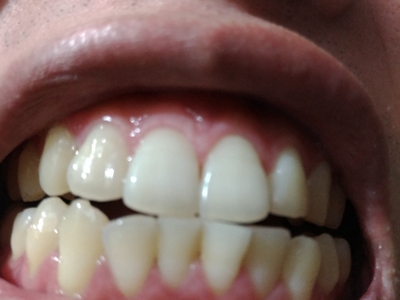

牙龈退缩露出淡黄色牙根图

牙龈退缩患者的牙龈退缩后,淡黄色牙龈明显露出。若进一步发展,易使对应位点的牙槽骨发生骨吸收,可能诱发龋齿、牙龈敏感、菌斑堆积等。